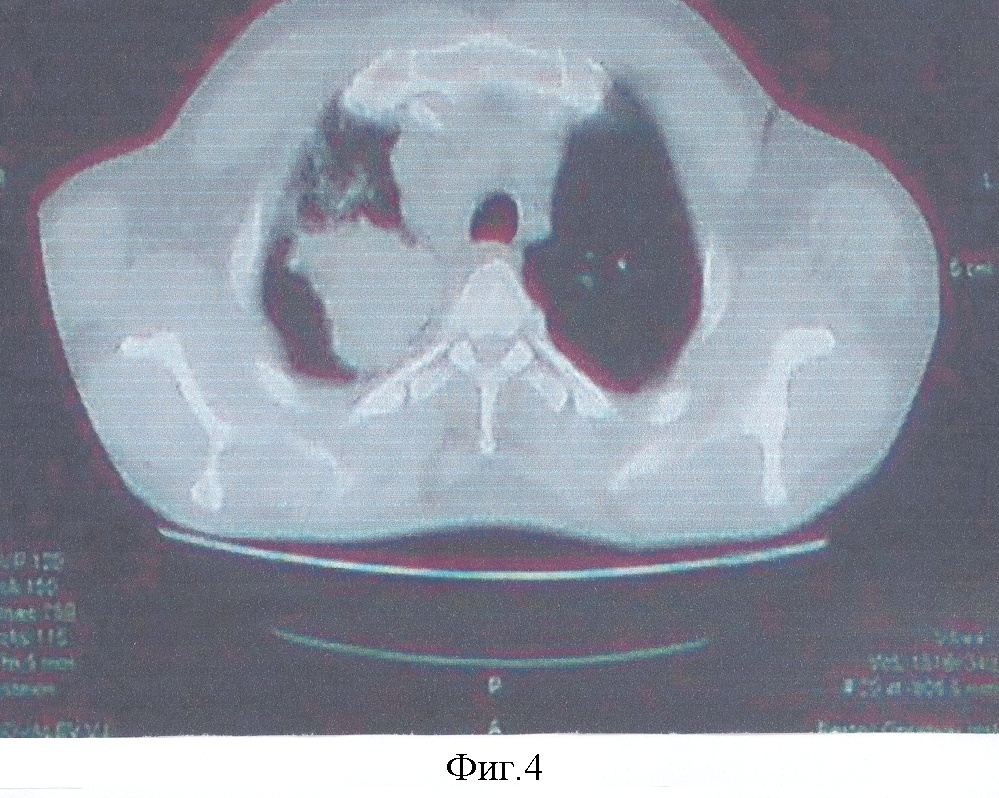

Фиг.4. Больной К-в. Компьютерная томограмма до лечения.